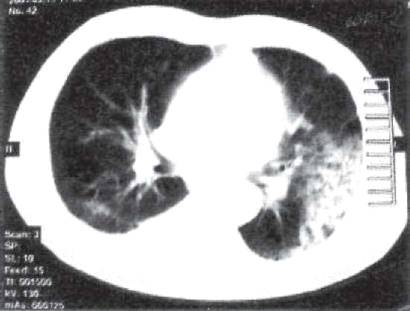

На КТ лобит иногда визуализируется в виде сплошного, почти однородного уплотнения доли легкого. В пораженной доле обнаруживают деформированные и частично обтурированные казеозными массами бронхи, а также множественные полости распада малого и среднего диаметра. Такую пораженную долю легкого иногда сравнивают с пчелиными сотами или хлебным мякишем (рис. 11.18). При прогрессировании лобита часто выявляют очаговую диссеминацию в противоположном легком, главным образом в IV и V сегментах (рис. 11.19).

Рис. 11.18. Лобит с множественными полостями распада в нижней доле левого легкого. КТ.